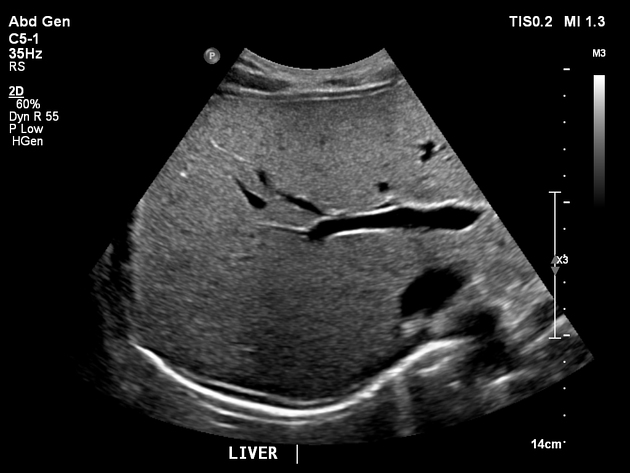

Liver Pathologies

Heatomegaly

Hepatomegaly